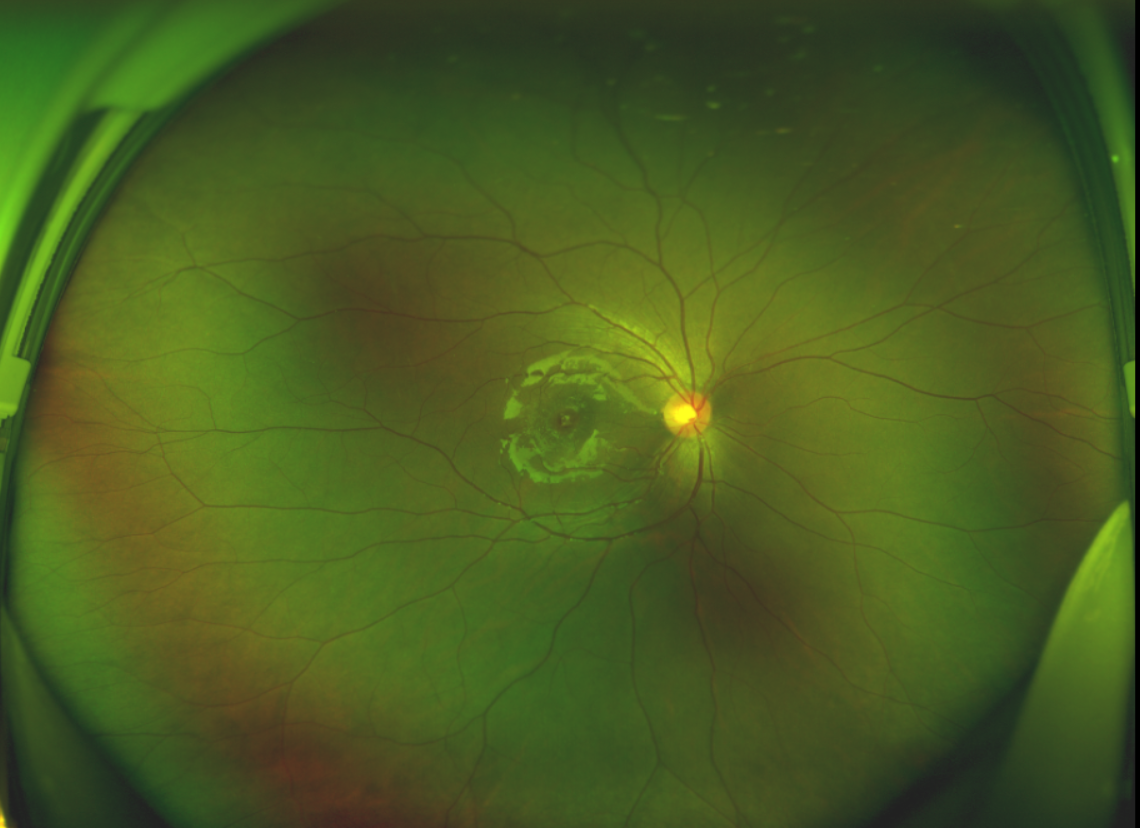

半年前的一次意外,誠(chéng)誠(chéng)(化名)右眼不慎受傷導(dǎo)致黃斑裂孔。從此,他的“視”界不再清晰,也不再有直線條……

黃斑位于視網(wǎng)膜正中心,是視覺(jué)最敏銳的區(qū)域,堪稱“眼底的心臟”,負(fù)責(zé)我們閱讀、駕駛、識(shí)別人臉等精細(xì)視覺(jué)。 當(dāng)黃斑區(qū)的神經(jīng)組織出現(xiàn)全層缺損,形成一個(gè)“孔洞”,即為黃斑裂孔,它會(huì)直接導(dǎo)致中心視力急劇下降、視物變形、視野中心出現(xiàn)暗區(qū)。

由于裂孔較小,當(dāng)?shù)蒯t(yī)院建議先觀察,看看裂孔是否能夠自愈。可半年時(shí)間過(guò)去了,誠(chéng)誠(chéng)傷眼的裂孔不僅沒(méi)有愈合的跡象,反而越來(lái)越大,這讓家長(zhǎng)的心揪得更緊了。

經(jīng)過(guò)詳細(xì)的檢查和評(píng)估,王曉波主任決定采用“內(nèi)界膜翻轉(zhuǎn)覆蓋聯(lián)合粘彈劑固定術(shù)”為誠(chéng)誠(chéng)進(jìn)行治療。

術(shù)中,醫(yī)生精細(xì)剝離黃斑區(qū)的內(nèi)界膜后,并非直接丟棄,而是巧妙地給它翻個(gè)面,讓它變成一塊天然“創(chuàng)可貼”,嚴(yán)密覆蓋在黃斑裂孔的表面。覆蓋的內(nèi)界膜像微型支架一樣撐住裂孔邊緣,防止它擴(kuò)大;同時(shí),這層膜本身含有能促進(jìn)生長(zhǎng)的“養(yǎng)分”,能顯著刺激裂孔周圍的視網(wǎng)膜組織像爬山虎一樣快速生長(zhǎng)、蔓延過(guò)來(lái),最終把裂孔“補(bǔ)”好。

除此之外,利用自體組織覆蓋為黃斑裂孔提供了理想的愈合環(huán)境,裂孔閉合速度顯著快于傳統(tǒng)方法。誠(chéng)誠(chéng)接受手術(shù)24小時(shí)后,檢查可見(jiàn)內(nèi)界膜瓣位置良好;術(shù)后1個(gè)月,黃斑裂孔已經(jīng)閉合,視力恢復(fù)到0.5;術(shù)后兩個(gè)月,視力進(jìn)一步提升到0.7。